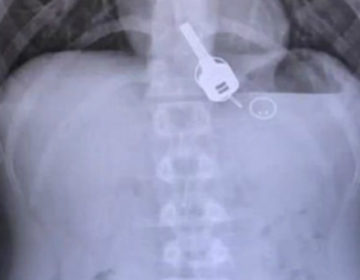

Ένιωθε έντονους πόνους στο στήθος, βρέθηκαν κλειδιά σφηνωμένα στον οισοφάγο του

Το αλκοόλ που είχε καταναλώσει τον έκανε να μην θυμάται